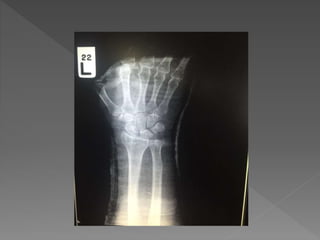

 Chiefcomplain : ปวดข้อมือซ้าย 2 ชั่วโมง PTA

› 2ชั่วโมง PTA ; ผู้ป่วยให้ประวัติว่า ขับรถมอเตอร์ไซด์ตก

หลุมแอ่งน้า เอามือซ้ายลง ขณะขับใส่หมวกกันน๊อค

ศีรษะไม่กระแทก ไม่สลบ จาเหตุการณ์ได้ตลอด หลังเกิด

เหตุปวดบริเวณข้อมือซ้าย Pain score 7/10 ข้อมือซ้าย

ผิดรูป บวม ขยับข้อมือได้ลาบาก ไม่มีอาการชา จึงส่งมา

รักษาที่รพ.มหาราช

o Leftforearmand wrist deformity

oLimit ROM of wrist joint

 Intra-articular fracture